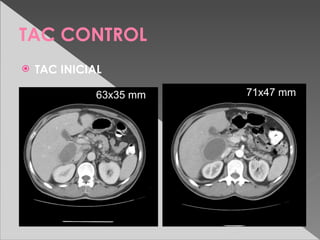

TAC CONTROL

   TAC INICIAL

63x35 mm                71x47 mm

TAC A LAS 2 Sem.